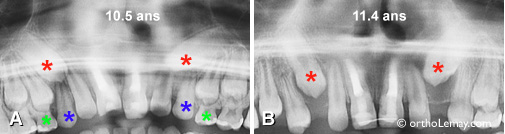

(A) À l’âge de 10 ans, les canines permanentes (astérisques * rouges) avaient une position similaire et étaient localisées dans une zone favorable pour permettre une bonne éruption à l’aide d’extractions sélectives, ce qui fut fait au cours des années suivantes. (les astérisques bleus indiquent les canines temporaires). (B) À 14 ans cependant, la canine gauche est bien sortie tandis que celle de droite s’est dirigée vers le centre et du côté du palais malgré l’extraction des dents temporaires. (C et D) Vues intra-orales montrant la position des canines permanentes.